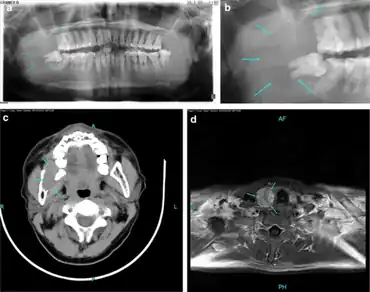

In contrast with primary hyperparathyroidism in adults, primary hyperparathyroidism in children is considered a rare endocrinopathy. Pediatric primary hyperparathyroidism can be distinguished by its more severe manifestations, in contrast to the less intense manifestations in adult primary hyperparathyroidism. Multiple endocrine neoplasia is more likely to be associated with childhood and adolescent primary hyperparathyroidism. The fundamental skeletal radiologic manifestation include diffuse osteopenia, pathologic fractures and the coexistence of resorption and sclerosis at numerous sites. Skeletal lesions can be specifically bilateral, symmetric and multifocal, exhibiting different types of bone resorption. Pathologic fractures of the femoral neck and spine can potentially initiate serious complications. Because pediatric primary hyperparathyroidism is frequently associated with pathologic fractures it can be misdiagnosed as osteogenesis imperfecta. Pediatric patients with primary hyperparathyroidism are best remedied by parathyroidectomy. Early diagnosis of pediatric primary hyperparathyroidism is all-important to minimize disease complications and start off timely and relevant treatment.[21][22]

- ↑ EL-Sobky TA, Ahmad KA, Samir S, EL Mikkawy DME (2016). "Primary hyperparathyroidism in a child: The musculoskeletal manifestations of a late presenting rare endocrinopathy". Egypt J Radiol Nucl Med. 47 (4): 1613–16. doi:10.1016/j.ejrnm.2016.09.002.